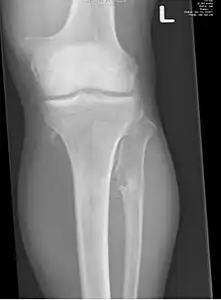

The diagnosis of HMO is based upon establishing an accurate correlation between the above-mentioned clinical features and the characteristic radiographic features. Family history can provide an important clue to the diagnosis. This is supplemented by testing for the two genes in which pathogenic variants are known to cause HMO namely EXT1 and EXT2. A combination of sequence analysis and deletion analysis of the entire coding regions of both EXT1 and EXT2 detects pathogenic variants in 70–95% of affected individuals.[3][4] The hallmark of radiographic diagnosis is the presence of osteochondromas at the metaphyseal ends of long bones in which the cortex and medulla of the osteochondroma represent a continuous extension of the host bone. This is readily demonstrable in radiographs of the knees.[3][1]

A noticeable lump in relation to an extremity may be the first presenting symptom. Multiple deformities can arise, namely coronal plane deformities around the knees, ankles, shoulders, elbows, and wrists. For example, genu valgum (knock knees), ankle valgus, ulnar bowing and shortening, and radial head subluxation are encountered. The majority of affected individuals have clinically manifest osteochondromas around the knee. Forearm involvement in HMO is considerable.[1][4] Furthermore, short stature may occur and is generally disproportionate. Such manifestations usually result from disruption of physeal growth especially that osteochondromas typically arise at the metaphyseal ends of long bones in close proximity to the physis.[1][4] Intra-articular osteochondromas of the hip can induce limitation of range of motion, joint pain and acetabular dysplasia.[2] Likewise joint pain at other locations and neurovascular compression can occur. Furthermore, functional disability in regard to activities of daily living can be a presenting feature. Spinal deformity pain or neurological compromise should arouse suspicion of involvement of the vertebrae.[3]